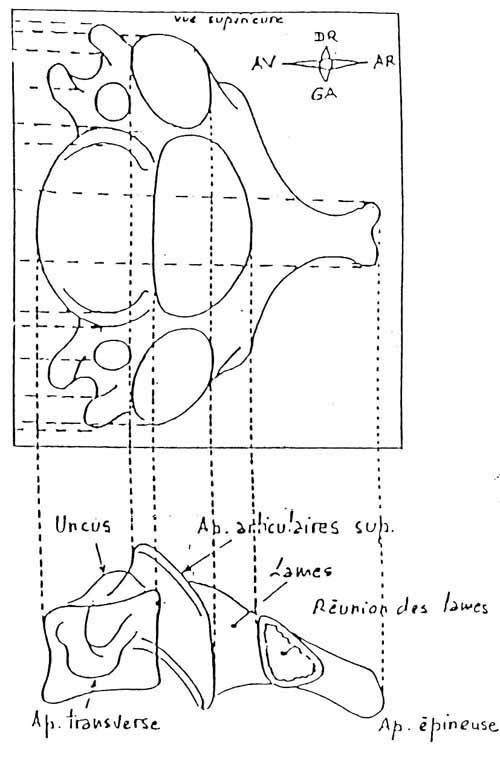

Commençons par le cervical, la suite viendra. Rachis cervical : radiographie, incidence antéro-postérieure

1. Axis

2. Processus transverse

3. Corps vertébral

4. Trou de conjugaison

5. Uncus

6. Disque intervétébralRachis cervical : radiographie, incidence de profil

Rachis cervical:  Rachis dorsal: Rachis dorsal:  Rachis lombaire: Rachis lombaire:   1. Processus articulaire supérieur 2. Pédicule droit 3. Processus transverse droit 4. Isthme 5. Processus articulaire inférieur 6. Lame opposée 7. Processus transverse opposé 8. Epineuse 9. Interligne articulaire postérieure 10. Processus articulaire inférieur opposé 11. Processus articulaire supérieur opposé Pour ce qui est de la radioanatomie; nous te laissons le soin d'apprendre tout cela grâce aux livres à ta disposition et à tes stages surtout!  Nous avions commencé une liste de livres de radiologie; à toi de t'en servir et bonnes recherches! Si tu souhaites trouver d'autres correspondances, si quelques détails t'interpellent n'hésite pas à poser des questions précises! Bon courage la marmotte!